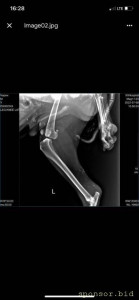

08.07.2022 г. передо мной на Варшавском шоссе сбили собаку, человек совершивший наезд даже не остановился и укатил дальше, я выбежала из машины, смогла остановить движение пары соседних полос, чтобы пес мог отползти на траву ( поднять и перенести не представлялось возможным, т.к. мне нельзя поднимать более 2 кг, более того непонятно что могла сделать собака в состоянии стресса и шока), после чего нашла парковку для машины и побежала к собаке, благо на тот момент несколько неравнодушных людей уже окружили его (это мальчик). Нами была вызвана полиция, составлено заявление ( но, думаем вряд ли кто-то будет этим заниматься.. так же сделан запрос в московскую службу видеофиксации, чтобы был сделан архив видео, если там есть камеры (тогда было не до этого, чтобы рассматривать есть ли они там), и в последствии приобщить к делу, или хотя бы найти того козла). Договорились со службой отлова, чтобы они на своей газели помогли довезти собаку до клиники шанс био, т.к. непонятно было что у нее с лапами, в клинике сделали рентген, несколько капельниц, обработали рану (т.к. задняя лапа разодрана до кости), взяли анализы, вкололи обезболивающие и отпустили.. т.к. у них нет стационара для бездомных, а так же хирурга, который мог бы сделать операцию. по заключению - кровоизлияние в глаз, открытая рана на левой заплюсне, вывих левого тбс (но вправить его нельзя, нужно делать операцию) порваны связки. по сумме в клинике оставили 14 500 руб. далее собаку отвезли в стационар надежда, с пятницы по воскресенье - обошлось в 10 552 руб (сам стационар, плюс лекарства, уколы и обработка ран, консервы, но он не ел). сегодня собаку возили на консультацию к хирургу в клинику беланта, было сделано дополнительно узи, на данный момент необходимо стабилизировать собаку, т.к. она еще в состоянии шока и с пятницы даже не ела, сейчас его опять повезли в стационар, необходимо еще делать уколы и обрабатывать рану, так же необходимо сделать 2 операции: на бедро (27200) и колено(55000), чтобы он смог передвигаться. в клинике заплатили 8167 с учетом лекарств. завтра планируется прием е еще одному хирургу в добрые руки, там по телефону озвучили цены на операции ниже чем в беланте, но нужен осмотр хирурга и его заключение. итого на данный момент на собачку ушло 33 219 руб. просим в сложившейся ситуации финансово помочь в судьбе пса, возможно найти ему любящих хозяев, на улицу его выкинуть уже просто невозможно, он там погибнет.. пес безумно умный, терпеливый, добрый, за все время ни разу не пытался агрессировать, укусить или что-то еще..

рентген

Помощь сбитой собачке - рентген 6.jpeg

Помощь сбитой собачке - рентген 1.jpeg

Помощь сбитой собачке - рентген 2.jpeg

Помощь сбитой собачке - рентген 3.jpeg

Помощь сбитой собачке - рентген 4.jpeg

Помощь сбитой собачке - рентген 5.jpeg